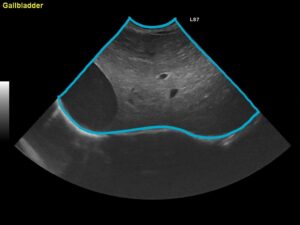

②超音波検査

超音波を用いて断片的に肝臓をみて評価する方法です。

下の写真の青線で囲っている部分が肝臓です。肝臓の形や腫瘍の有無、門脈体循環シャントがないか確認します。また胆のう内の胆汁の性状や胆管の状態を診ることもできます。